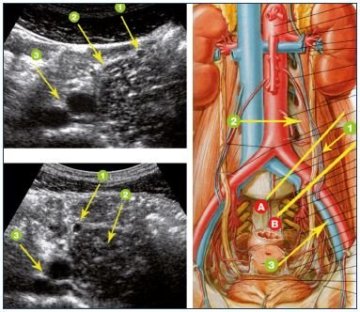

Hastalığın tanısı konulurken öncelikle diğer karışabilecek hastalıklar ekarte edilmelidir. Hastalığın pelvik venöz konjesyon tablosu olduğu düşünüldüğünde buna yönelik araştırmalar basitten komplekse doğru ilerletilmelidir. Bu tetkik sonuçları kombine edilerek, problemin hangi toplardamardaki kaçaktan ortaya çıktığı gösterilmelidir. Bunun için öncelikle doppler ultrason ile karın içi ve kasık bögesindeki toplardamarların yapısı ve kaçaklar değerlendirilmelidir. Daha sonra manyetik rezonans (MR) görüntüleme veya tomografi yapılarak karın içi organ ve damarların yapısı değerlendirilir.

Uterus etrafında çok sayısda 4mm'den geniş büklüntülü variköz yapıların görülmesi veya ovarian venin 5-6mm'den geniş olarak ölçülmesi tanı koydurucu olmaktadır.